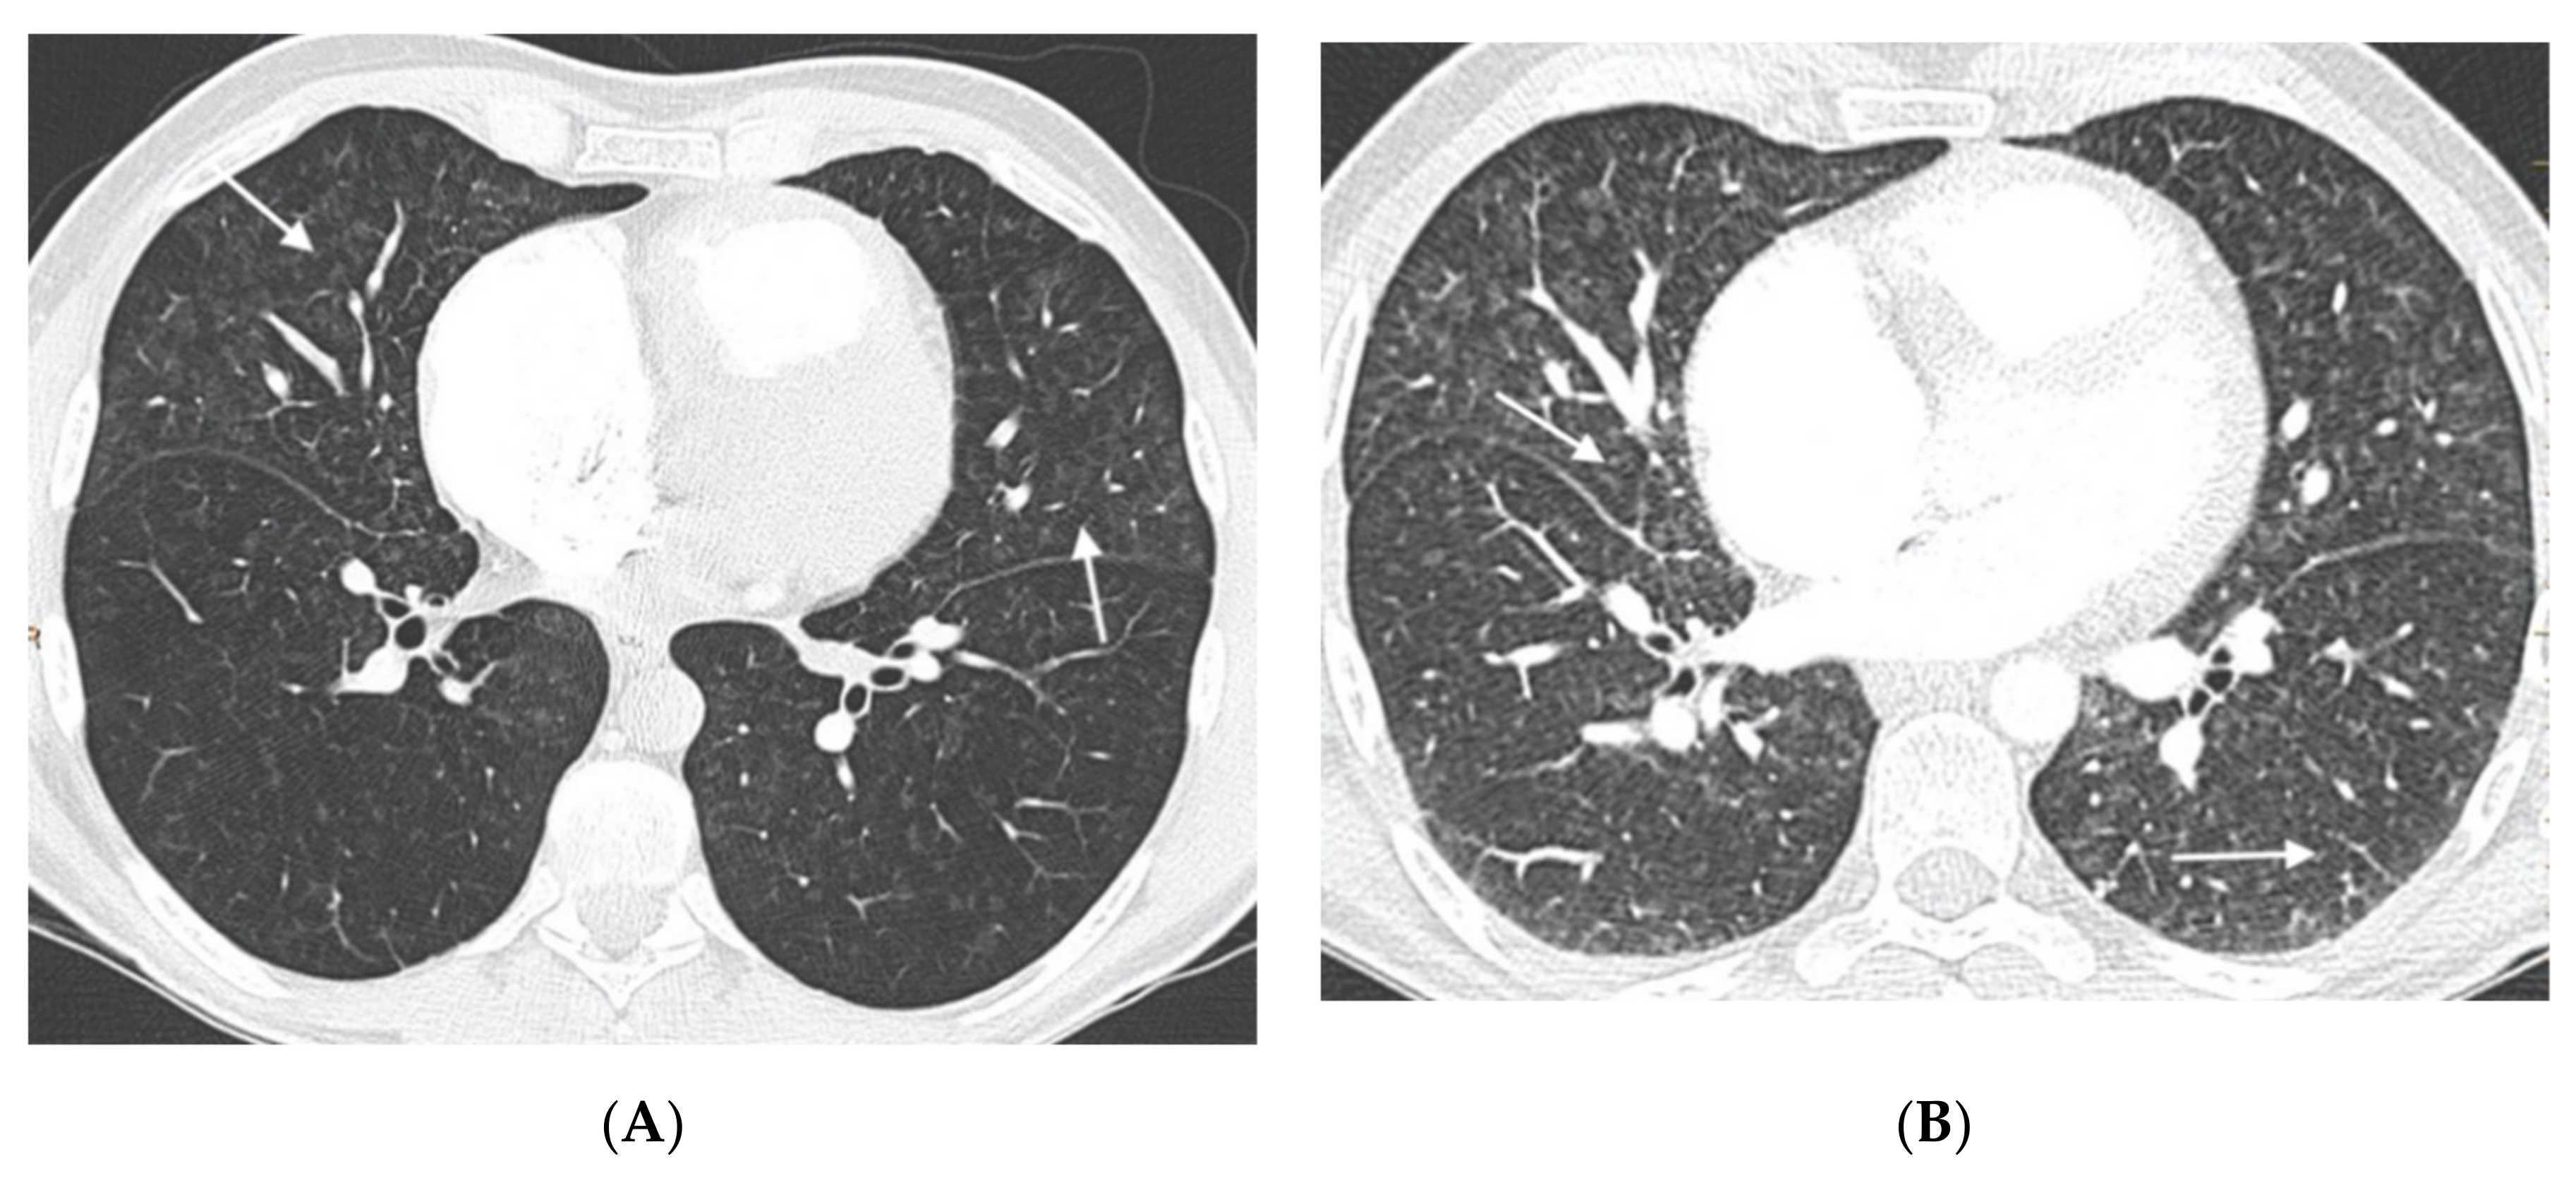

Figure 4.

Fifty-five-year-old woman with sporadic PVOD histologically diagnosed after double lung transplantation. The patient had three typical MDCT findings and in situ thrombus in the left main pulmonary artery (normal ventilation-perfusion scintigraphy excluded CTEPH). (A) Dilation of the pulmonary artery (PA) trunk with thrombus in situ in the left main pulmonary artery (arrows); (B) ground-glass centrilobular nodules in both upper lobes (arrows) and septal lines (short arrows); (C) left hilar adenopathy (arrow). PA: pulmonary artery.